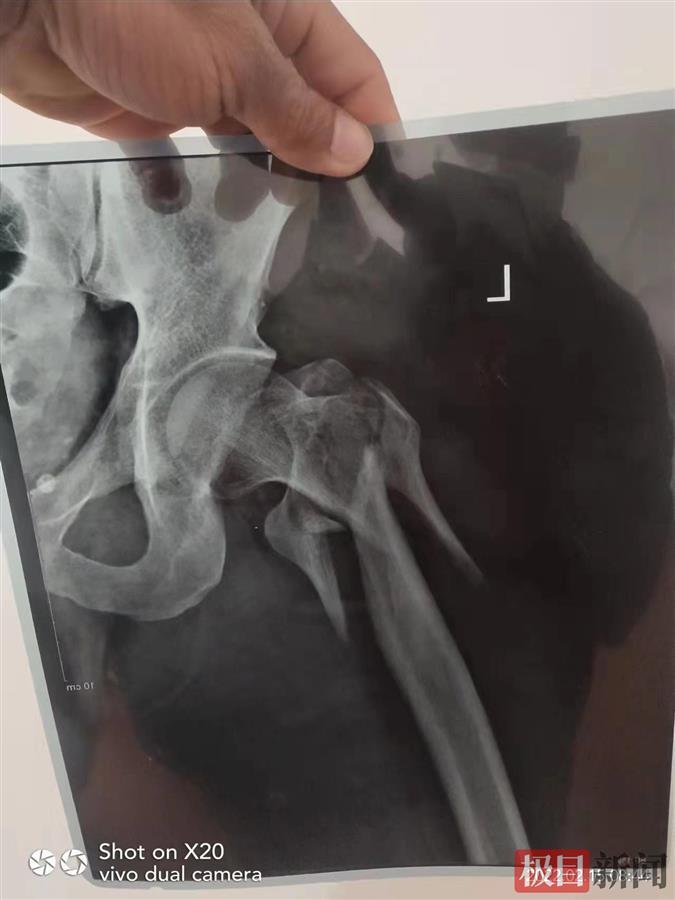

欧阳受伤情况

在缅甸,欧阳在被软禁的地方从4楼一跃而下,身上两处粉碎性骨折。